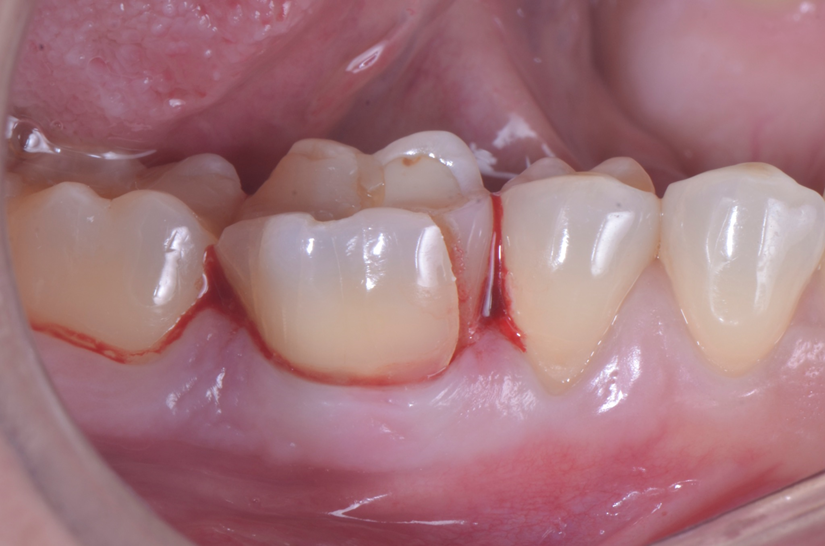

O paciente apresentou fratura vertical mésio-distal no elemento 46. Foi planejada a exodontia minimamente traumática e instalação imediata do implante Maestro Superiore (Implacil Osstem) utilizando uma guia prototipada. Após a exodontia, o implante foi instalado seguindo o protocolo de cirurgia guiada. O GAP vestibular foi preenchido com o Extra Graft. Um cicatrizador personalizado impresso com haletas facilitadoras foi capturado com resina flow e instalado. Após 30 dias, foi realizado escaneamento indireto para obtenção do perfil de emergência, utilizando protocolo digital com sobreposição do cicatrizador escaneado para confecção da coroa definitiva em zircônia policristalina estabilizada por ítria.